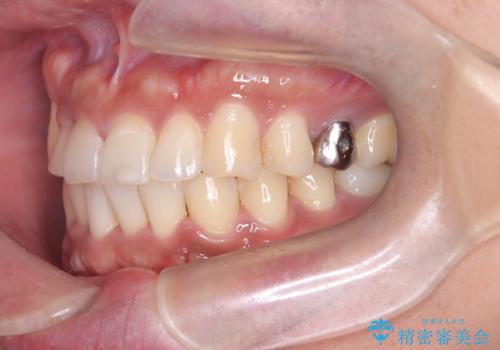

【ワイヤー矯正】八重歯と下の歯の凸凹を治したい

- 主訴:右上の八重歯と、下の歯の凸凹を治したい

上顎右側第一小臼歯と下顎右側第一小臼歯を抜歯しワイヤー矯正を行いました。

右側2級、左側1関係だったため、右側上下第一小臼歯を抜歯し、ワイヤー矯正を行いました。